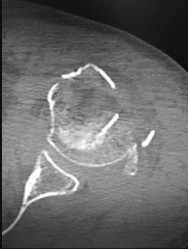

Question 24

A 72-year-old woman with chronic pseudoparalysis of the shoulder undergoes the procedure shown in the radiograph below. Which of the following is the most commonly reported radiographic complication specifically associated with this biomechanical implant design?

Explanation

The image depicts a reverse total shoulder arthroplasty (RTSA). Scapular notching, caused by mechanical impingement of the medial humeral metaphysis against the inferior scapular neck during adduction, is the most common radiographic complication. It is historically highest with medialized glenosphere and inlay humerus implant designs.